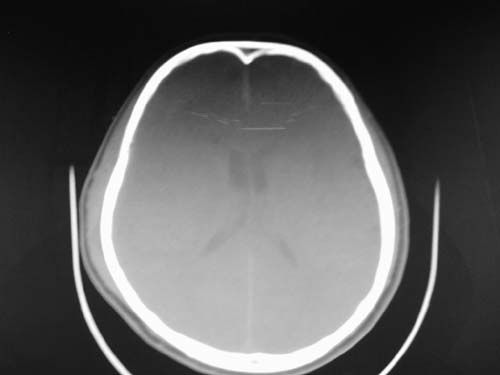

脑中线内血肿,是硬膜下的吗?

脑中线内血肿——硬膜下血肿。

脑中线内血肿——硬膜下血肿。我们一般认为中线即可是硬膜下,也可是蛛网膜下腔的。边缘锐利,张力高的考虑硬膜下的,边缘模糊的,考虑下腔的。如果有老师有肯定的答案,麻烦下给我发个短信

硬膜下血肿,有颅骨骨折

支持镰旁硬膜下血肿,颅骨骨折,头皮损伤.

这个病人年龄不小吧,右侧脑沟不清,中线结构稍有左移,右侧额颞顶及右镰旁硬膜下血肿,另有蛛血,骨折。

外伤后引起的颅骨骨折、硬膜下血肿、皮下血肿,颅骨骨折引起的矢状窦破裂,形成大脑纵裂内血肿。